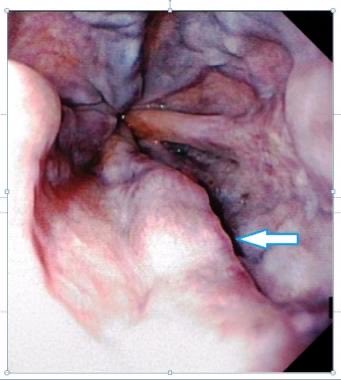

✳️ يتميز بتشويه الكبد وتشكيل العديد من العقد في الكبد مثل ما هو موضح بالصورة

والعلامات موجود بالصور للمختصين 👨🏻‍⚕️🩺